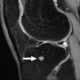

Multiple enchondromas

An enchondroma is a benign cartilage tumour found inside bones. Typically, enchondroma is discovered on an X-ray scan. [Source: Wikipedia ]